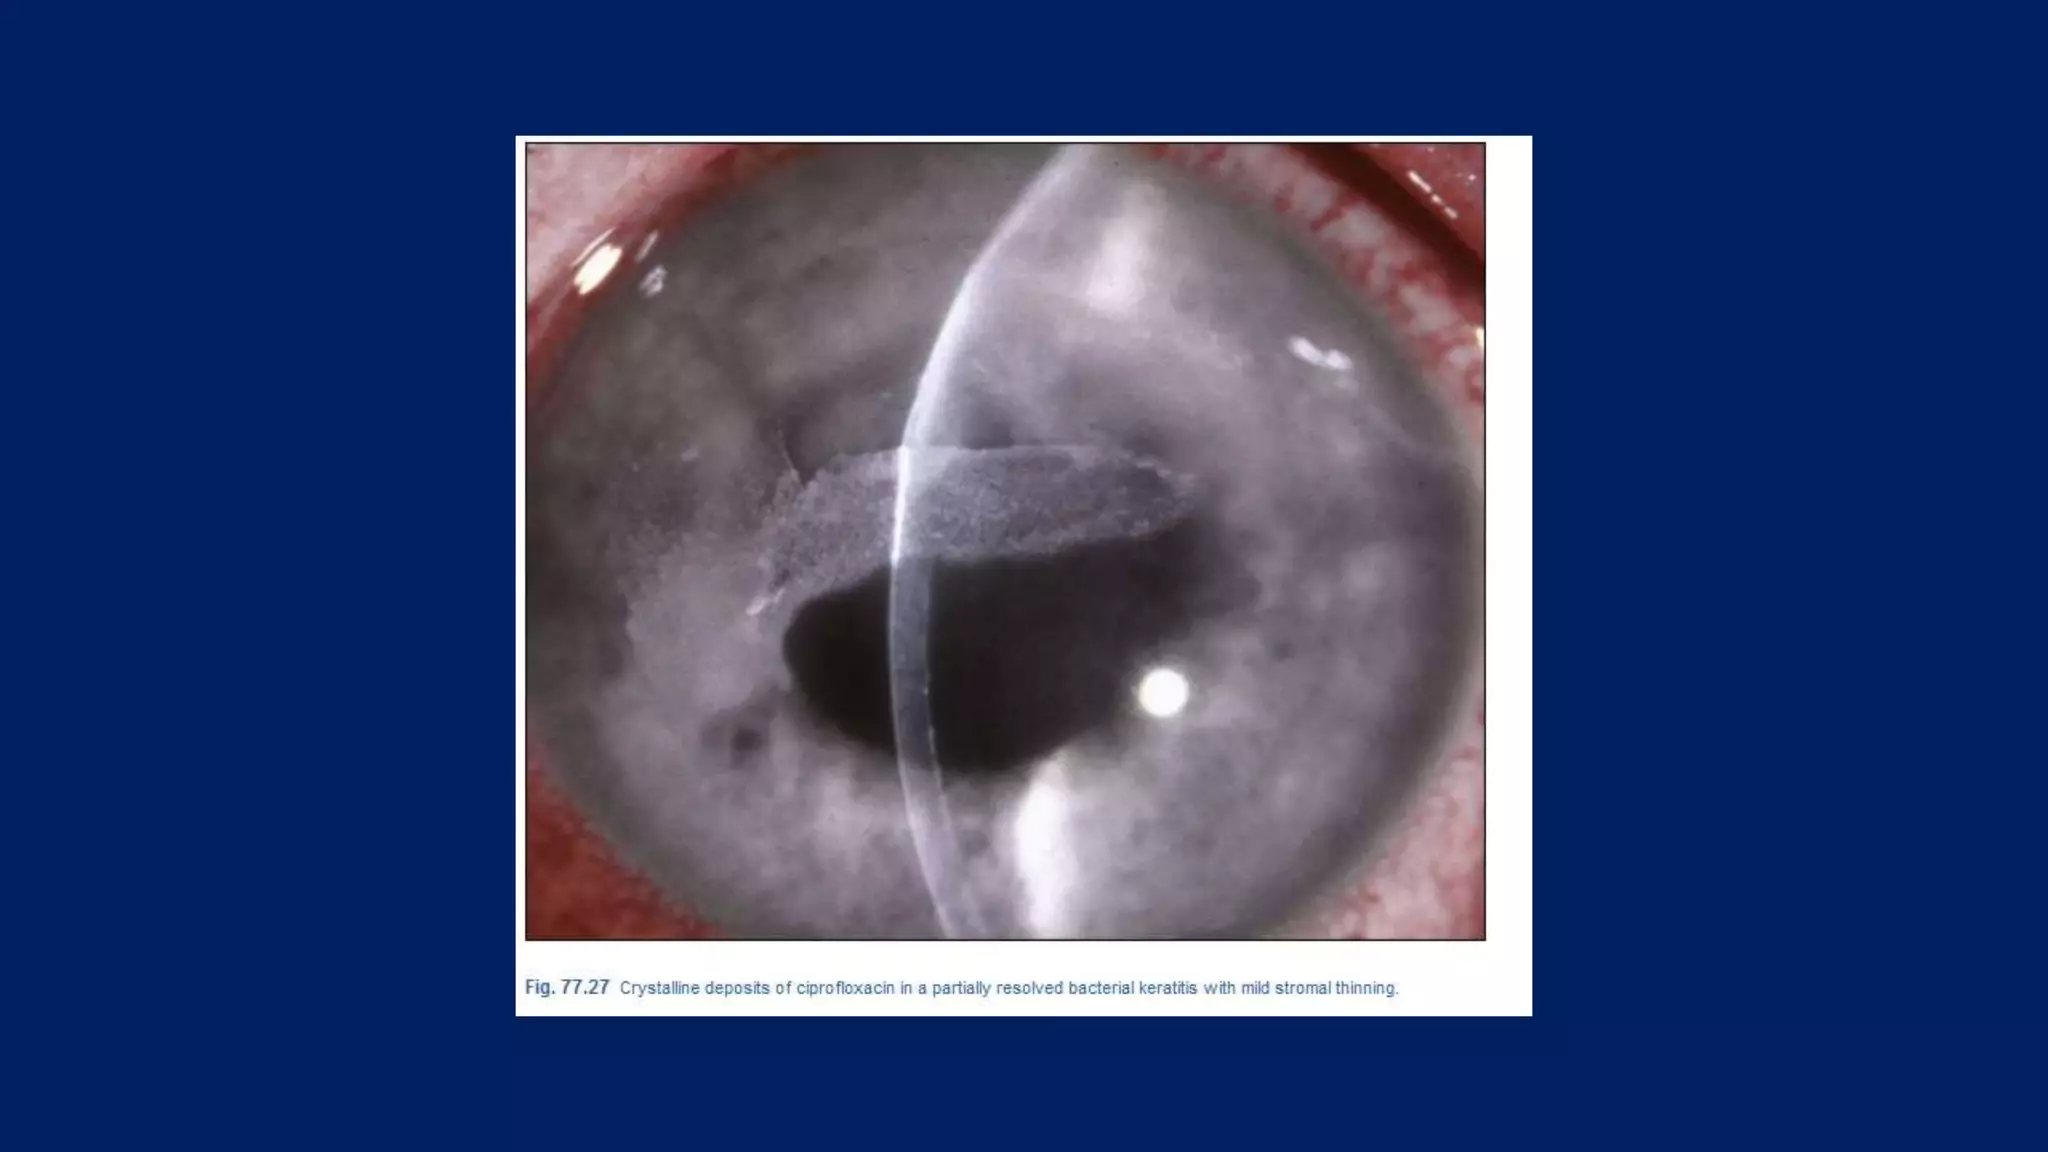

• Side effects of fluoroquinolone are minimal. The incidence of

ocular discomfort for patients receiving topical fluoroquinolone

is significantly less when compared with patients receiving

fortified antibiotics (5.7% vs 13.4%). Crystalline corneal

deposits after use of ciprofloxacin, norfloxacin, and ofloxacin

have been reported. These deposits occur with higher

frequency in ciprofloxacin-treated eyes, consistent with the pH

solubility profile of fluoroquinolone compounds in that

ciprofloxacin is less soluble at physiological pH. However, these

deposits are precipitates of the antibiotics and do not appear to

diminish the antimicrobial effect.